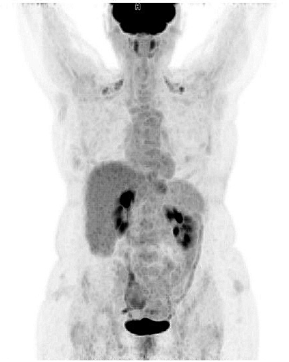

The patient was referred to a hematologist for proper staging and therapy. The positron emission tomography-computed tomography (PET/CT) scan showed a normal findings with low metabolic activity in the area of the wound infection (Figure 4). Bone marrow biopsy was negative. According to the Lugano score [7], the patient was diagnosed with Stage I of the disease.

Seven cycles of R-CHOP (rituximab, cyclophosphamide, doxorubicin, vincristine, and prednisolone) regimen were given to the patient as the first line of treatment. Post-chemotherapy PET/CT scan presented with normal findings. The patient is still in complete remission after the combined treatment with surgery and chemotherapy and regular future checkups are scheduled.